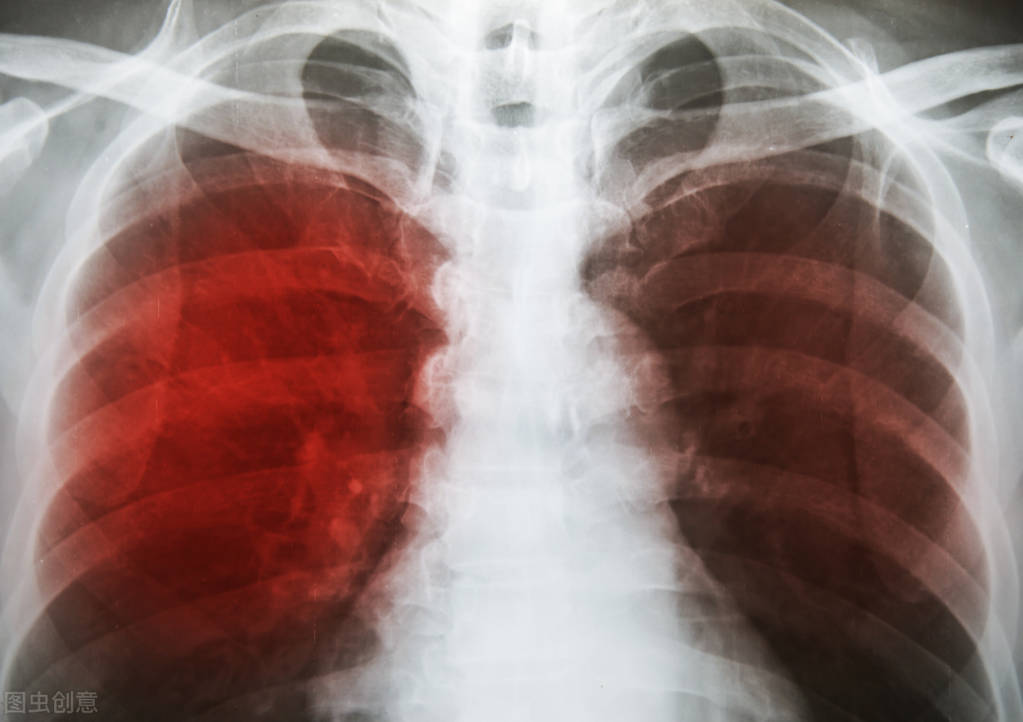

她患上肺结核的时间是在08年,当时她家里人都说医疗水平提高了,这种病都算小病了,只要配合医生随便就治好了。柯女士来到了当地的结核病医院治疗,他的病情比一般人要严重很多,除了肺结核常见的发烧咳嗽之外,肺部影像上还显示她的肺部有很大的空洞,连着三个月,每天就是吊药水,吃药,渐渐地她也从一开始的发烧走不了路,一直咳痰的症状中脱离出来了。出院回家之后,开始保守治疗,边打针边口服抗结核的药物。

随着年龄的增大,柯女士咳血的次数越来越频繁了,第二次治疗结束后,再次复查的结果,出乎他们的意料,本来他体内的肺结核病灶就已经开始钙化了,而且空洞也在变小,但是这次复查却显示,肺部出现了大量的曲霉血菌球,碍于县里面的医疗水平,这种病是很罕见的,加上家庭经济实力有限,最后去了省里的结核医院治疗。

但是要注意的是,这类患者在做痰涂片的时候,不一定能从上面找到结核杆菌,可能仅仅表现为患者身体出现发热、咳嗽、咯血、乏力、消瘦的症状,亦或是胸部ct的影像显示边缘模糊不清的斑片状阴影或空洞。如果拍出来的胸片上面仅仅表现为钙化或者硬结的时候,在做完三次痰涂片仍然显示为阴性的话,那么这就是无活动性肺结核,这种类型的肺结核不具备传染性,这也是大部分的结核杆菌携带者所处的类型。一般来说虽然活动性肺结核患者在做痰涂片时能被检测出阴性的,但是检测出阳性的患者传染性要更强。